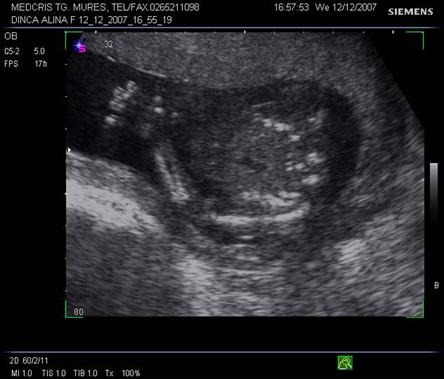

Membrele

Oasele lungi isi incep osificarea in diafiza, centrii de osificare pot fi pusi in evidenta incepand cu 9 - 10 saptamani la ecografia transvaginala si cca 12 saptamani la ecografia transabdominala. Epifiza cartilaginoasa apare, doar cu echipament de buna calitate, ca o zona hipoecogena, in trim. II si III.[1,7,8,12]

Femurul reprezinta o tinta de explorare, in special pentru biometrie, iar tibia si fibula trebuie evidentiate la ambele gambe. Ambele femure vor fi simetrice si egale. Centrii de osificare femural distal si proximal tibial apar la cca 32 - 33 saptamani, respectiv la 36 - 37 saptamani.

Piciorul trebuie evidentiat in continuarea gambei in sectiune sagitala. Aspectul plantar cu 5 degete, se obtine prin rotatia cu 90% a transductorului, dar necesita timp pentru imagine corecta. Planta nu poate fi evidentiata in asociere cu tibia, decat in prezenta unei deformitati ale membrelor.[1,7,12]